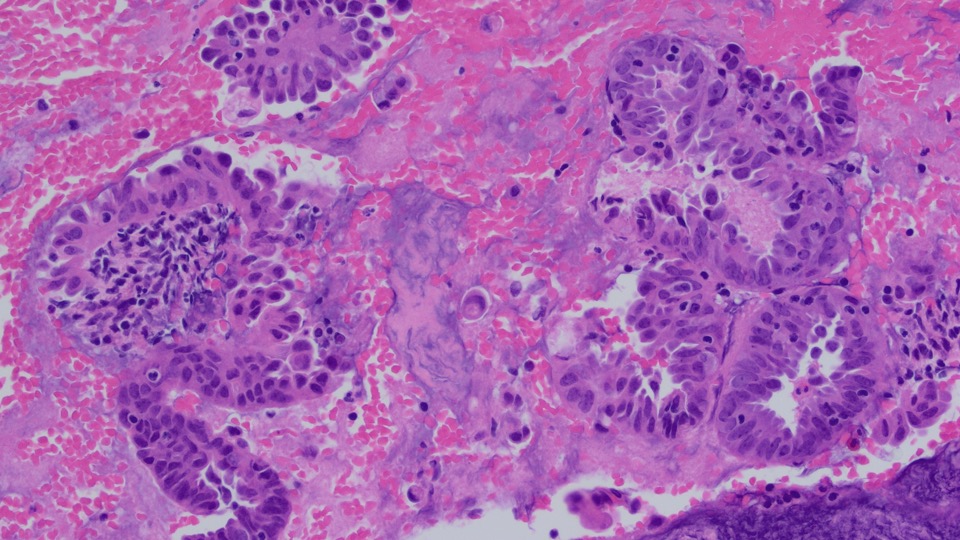

Endometrial curetting specimen show detached aggregates of exuberant architecturally simple papillary/pseudopapillary proliferation of the endometrium.

Papillary proliferation of the endometrium (PPEs) is an uncommon lesion characterized by papillae with fibrovascular stromal cores covered by cytologically benign epithelium. The changes are closely related to hormonal treatment, endometrial polyps, and epithelial metaplasias.